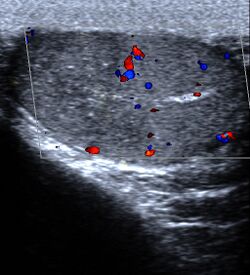

Segmental testis infarction in a patient presenting with right testis pain.

Many other less common conditions can lead to testicular pain. These include inguinal hernias, injury, hydroceles, degenerative disease of lumbar spine,[10] disc herniations,[11] and varicoceles among others. Testicular cancer is usually painless.[12] Another potential cause is epididymal hypertension (also known as "blue balls").[13]

Imaging

Ultrasound is useful if the cause is not certain based on the above measures.[15] If the diagnosis of torsion is certain, imaging should not delay definitive management such as physical maneuvers and surgery.[7]